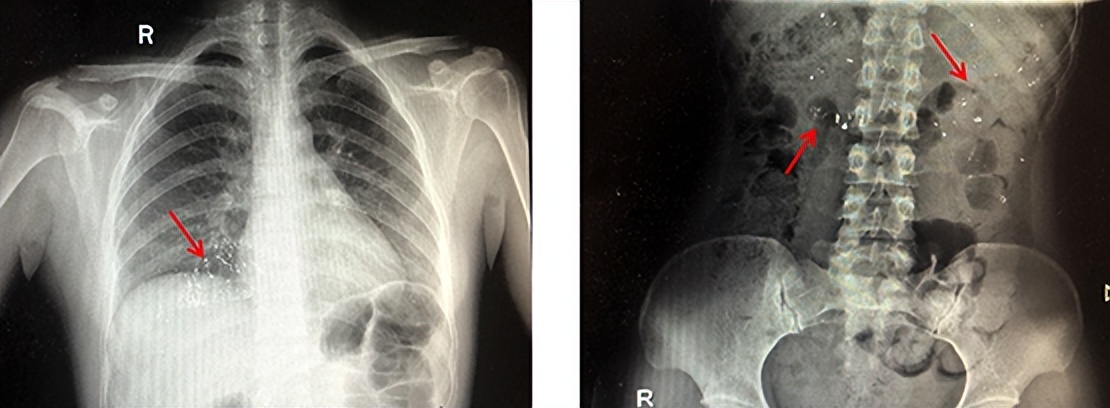

医生解释,水银体温计是由玻璃和金属汞构成,咬碎后的碎片可能会导致口腔、咽喉部、胃肠道黏膜的损伤,严重者甚至会导致穿孔。

水银经胃肠道吸收甚微,但误吞水银者如果胃肠道黏膜有溃疡伤口,水银便会经溃疡或者伤口立刻进入人体血液,这样被吸收的汞会产生较大的毒性,严重可危及生命安全。

除了水银温度计,学龄前期的孩子对外界充满好奇心,但是没有安全意识,硬币、纽扣、发夹、电池、小磁铁、枣核、小钉子等都是危险品,这些异物容易损伤消化道、气管,甚至引起窒息等危及生命,因此,家长应时刻看护好孩子,避开或避免接触危险异物。一旦出现误吞或误吸异物,请及时就医。